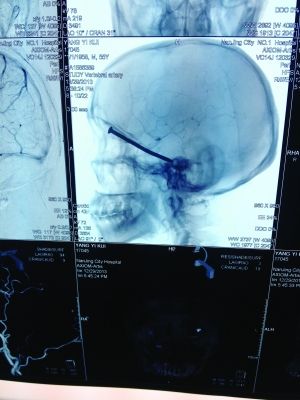

CT投影

前幾天,市民楊先生在家翻新地板時,眼中突然飛入“異物”。去醫(yī)院檢查,發(fā)現(xiàn)這“異物”竟是一根長達(dá)8厘米的鐵釘!好在鐵釘錯開了楊先生頭部的各種大血管,醫(yī)生得以順利將其取出。

CT投影結(jié)果,把大家嚇了一跳:楊先生腦子里居然有一根長釘,從眼眶一直“伸”到了接近后腦勺的位置!鐵釘細(xì)長略帶彎曲,長達(dá)8厘米。根據(jù)推測,鐵釘應(yīng)該是從上眼眶的縫隙中飛入,一直插進(jìn)腦顱中,末端還有一個小小凸出的釘帽。